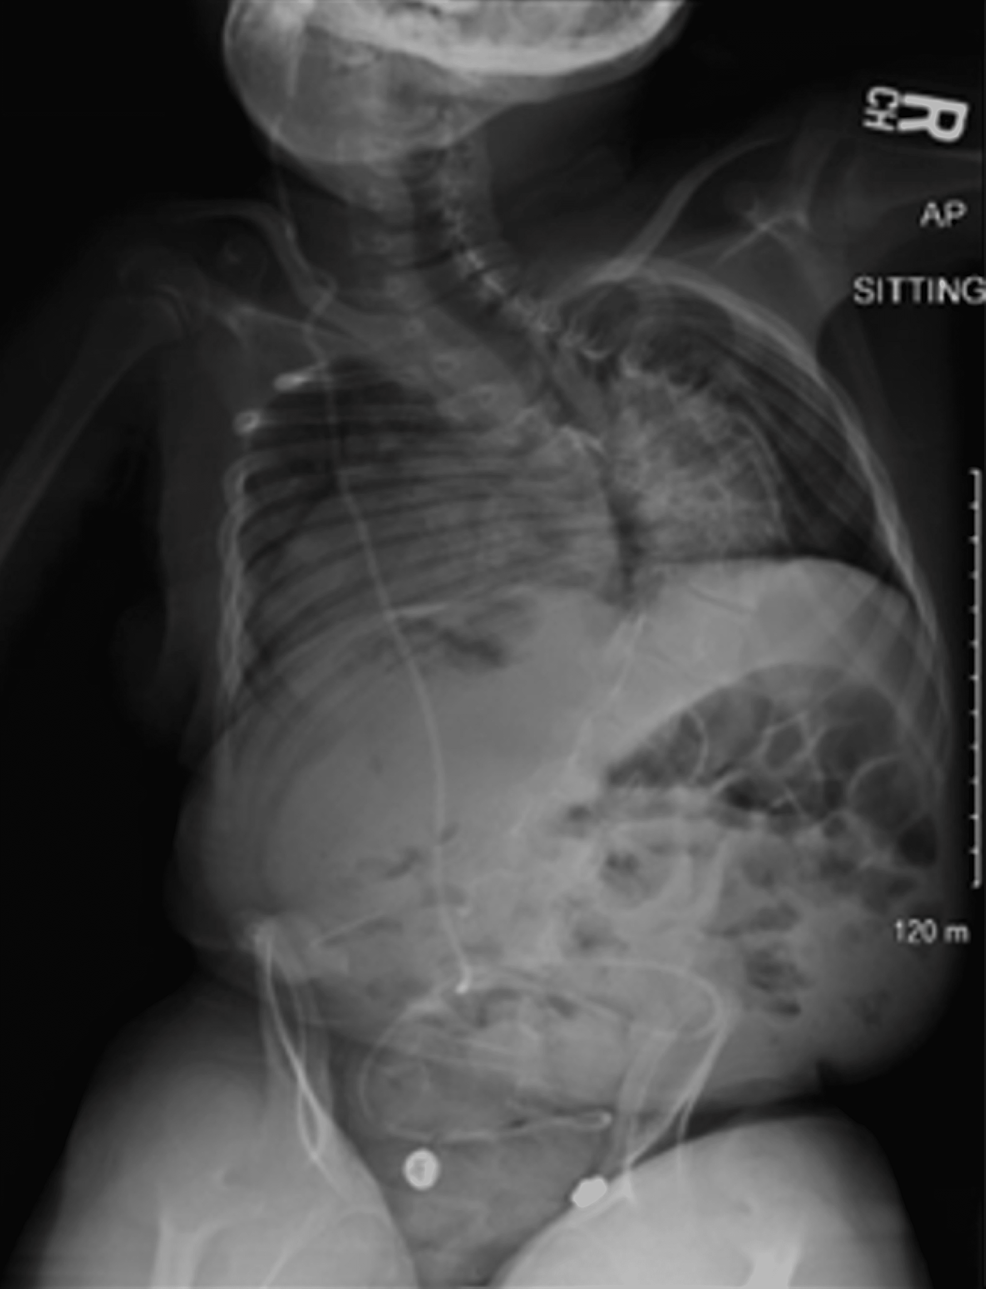

Idiopathic EarlyOnset Scoliosis Treated With Magec Rods What to Do After the Lengthening Magec Rod Lengthening Cpt Code I am looking for the best code to use for the lengthening of spinal instrumentation growth rods. There seems to be nothing. So report code 20696, which reimburses at $1,248 (national allowable rate), just once to all surgical services related to the limb. The magec system comprises a magnetically distractible spinal rod implant and an external remote controller, which lengthens. Magec Rod Lengthening Cpt Code.

After MAGEC rod insertion (A and B) and 4 years after insertion (C and D). Download Scientific Magec Rod Lengthening Cpt Code The fda has classified the magec system under product code pgn. So report code 20696, which reimburses at $1,248 (national allowable rate), just once to all surgical services related to the limb. There seems to be nothing. I am looking for the best code to use for the lengthening of spinal instrumentation growth rods. The magec system comprises a magnetically. Magec Rod Lengthening Cpt Code.